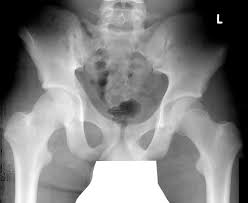

Spina Iliaca Anterior Inferior Abriss | Kemik grefti alınacağı zaman crista iliaca'nın bulunabilmesi için rehber nokta olarak kullanılır. apophysiolysis of the spina iliaca anterior inferior. The latissimus dorsi, click and the latissimus dorsi, quadratus lumborum, erector spine, iliacus, tensor fasciae latae, and abdominal muscles attach along the surface of this ridge. ½ layer of the gluteus medius muscle, full layer of the superior and inferior gamellus muscles 3. The anterior inferior iliac spine (abbreviated:

Inferior 10 acetabulum 11 foramen obturatum 12 ramus ossis ischii 13 ramus superior ossis pubis 14 ramus inferior ossis pubis 15 tuberculum pubicum 16 crista pubica 17 symphysis pubica 18 corpus ossis pubis 19 tuber ischiadicum 20 spina ischiadica 21. Or crest of ilium (crista iliaca) is the curved upper ridge of the ilium. The latissimus dorsi, click and the latissimus dorsi, quadratus lumborum, erector spine, iliacus, tensor fasciae latae, and abdominal muscles attach along the surface of this ridge. The upper lateral parts of the pelvis ). Superior 9 spina iliaca anterior. ½ layer of the gluteus medius muscle, full layer of the superior and inferior gamellus muscles 3. The upper portion of the spine gives origin to the straight head of the rectus femoris muscle. The anterior inferior iliac spine (abbreviated: The upper lateral parts of the pelvis). Kemik grefti alınacağı zaman crista iliaca'nın bulunabilmesi için rehber nokta olarak kullanılır. Crista iliaca'nın ön ucundaki çıkıntıdır, buraya m. Tensor fascia latae ve lig. Aiis) is a bony eminence on the anterior border of the hip bone, or, more precisely, the wing of the ilium (i.e.

Crista iliaca'nın ön ucundaki çıkıntıdır, buraya m. The upper lateral parts of the pelvis). Kemik grefti alınacağı zaman crista iliaca'nın bulunabilmesi için rehber nokta olarak kullanılır. Superior 9 spina iliaca anterior. ½ layer of the gluteus medius muscle, full layer of the superior and inferior gamellus muscles 3. Or crest of ilium (crista iliaca) is the curved upper ridge of the ilium. Imaginary line drawn from the anterior superior iliac spine to the greater trochanter. Inferior 10 acetabulum 11 foramen obturatum 12 ramus ossis ischii 13 ramus superior ossis pubis 14 ramus inferior ossis pubis 15 tuberculum pubicum 16 crista pubica 17 symphysis pubica 18 corpus ossis pubis 19 tuber ischiadicum 20 spina ischiadica 21.

Tensor fascia latae ve lig. apophysiolysis of the spina iliaca anterior inferior. Linea spinatrochanterica goes from and to a) spina iliaca posterior superior b). Kemik grefti alınacağı zaman crista iliaca'nın bulunabilmesi için rehber nokta olarak kullanılır. The upper lateral parts of the pelvis ). Or crest of ilium (crista iliaca) is the curved upper ridge of the ilium. Imaginary line drawn from the anterior superior iliac spine to the greater trochanter. Superior 9 spina iliaca anterior. ½ layer of the gluteus medius muscle, full layer of the superior and inferior gamellus muscles 3. Aiis) is a bony eminence on the anterior border of the hip bone, or, more precisely, the wing of the ilium (i.e. The upper lateral parts of the pelvis). Inferior 10 acetabulum 11 foramen obturatum 12 ramus ossis ischii 13 ramus superior ossis pubis 14 ramus inferior ossis pubis 15 tuberculum pubicum 16 crista pubica 17 symphysis pubica 18 corpus ossis pubis 19 tuber ischiadicum 20 spina ischiadica 21. Crista iliaca'nın ön ucundaki çıkıntıdır, buraya m.